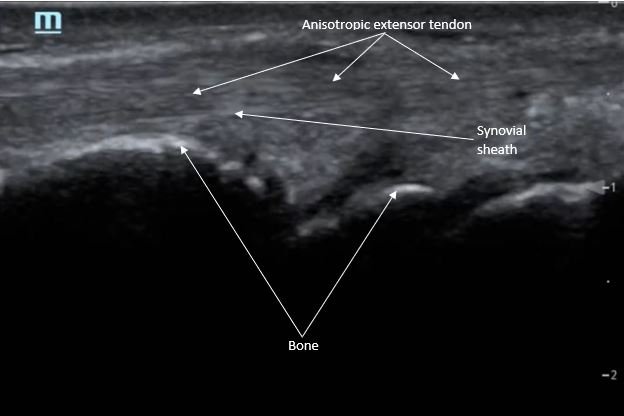

Point-of-care ultrasound of the dorsal aspect of the left hand reveals a heterogenous hypoechoic fluid collection surrounding the extensor tendons (axial view) within the retinaculum consistent with edema. Longitudinal view shows anechoic fluid within the tenosynovium which is located between the anisotropic extensor tendon and linear hyperechoic synovial sheath. Longitudinal view also shows some cobblestoning, or tissue edema, superficial to the anisotropic extensor tendon. The patient’s contralateral right dorsal hand was scanned in a longitudinal view and shows no cobblestoning or hypoechoic fluid under the synovial sheath. The patient was diagnosed with tenosynovitis, and started on intravenous antibiotics.

There is a paucity of literature on extensor tenosynovitis compared with flexor tenosynovitis. The diagnosis of tenosynovitis of the wrist is often clinical using Kanavel’s cardinal signs developed in 1912, though this was developed for flexor, and not extensor tenosynovitis.1 More recently, ultrasound has been used to diagnose tenosynovitis with a sensitivity of 94% and has been shown to be more sensitive than clinical exam.4,5,6 Ultrasound findings may include hypoechoic to anechoic fluid and cobblestoning of the soft tissues, a thickened tendon sheath, and abnormal hypoechoic material within the synovial sheath.5 These ultrasound findings are best seen using a high frequency linear probe oriented in the transverse and longitudinal planes over the dorsal aspect of the hand.6 Our patient’s ultrasound demonstrated cobblestoning of the soft tissues and abnormal hypoechoic material within the synovial sheath; however, we did not measure synovial sheath thickness. While superficial cobblestoning is commonly seen in cellulitis, a thickened synovial sheath and/or abnormal hypoechoic material within the synovial sheath should prompt consideration of tenosynovitis.